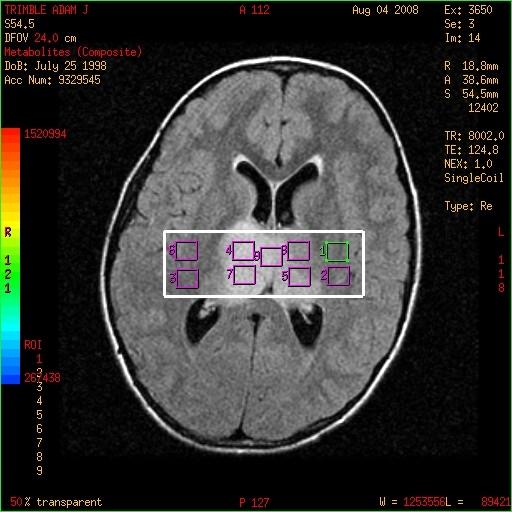

• Multivoxel

• MRSI

• “MR Spectrographic Imaging”

• CSI

• “Chemical Shift Imaging”

Decide whether Single vs Multivoxel is needed:

Multiple voxels (minimum volume of each voxel 1.0 cm) acquired at the same time. Less influenced by gradient-induced distortions therefore better baseline. Greater “voxel bleeding” therefore quantification not precise.

Multivoxel : Remember to manually screen save your ROI image.